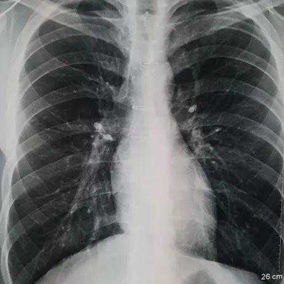

The patient is a 19-year-old male who underwent surgery for congenital heart disease at the age of 9. During the surgery, the middle part of his sternum was split, compromising the integrity and stability of the chest wall structure. Additionally, inadequate fixation of the chest wall during the closure of the incision led to the development of secondary pectus carinatum, with the chest wall protruding forward within a year after the surgery. Over time, the protrusion became increasingly severe, and by the eighth year after the surgery, the patient began experiencing breathing discomfort.

The chest wall exhibits a large area of prominent and bilaterally symmetrical protrusion, predominantly in the upper half. There are also mild depressions on both sides of the lower half of the chest wall.